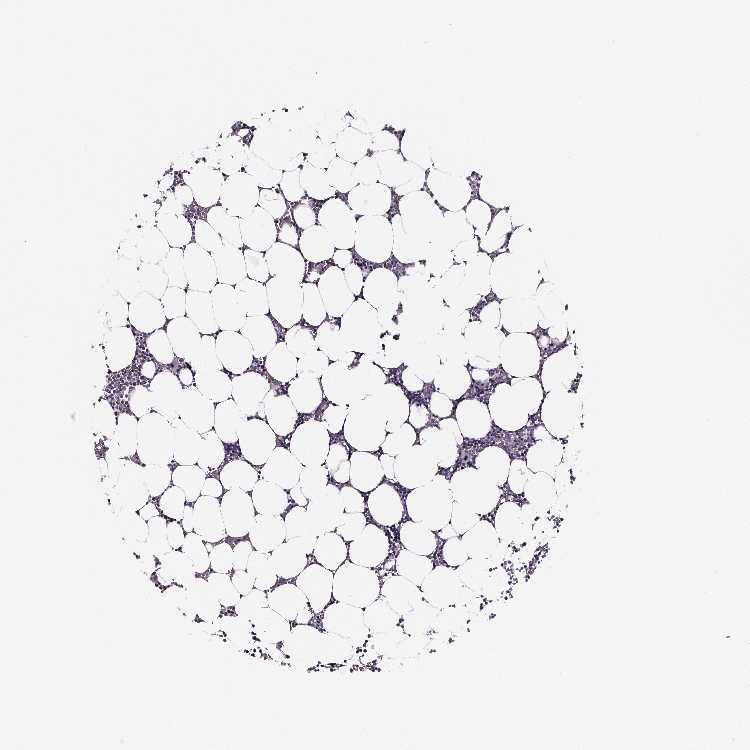

BONE MARROW - Antibody stainingi

Antibody staining in the annotated cell types in the current human tissue is reported as not detected, low, medium, or high, based on conventional immunohistochemistry profiling in selected tissues. This score is based on the combination of the staining intensity and fraction of stained cells.

Each image is clickable and will lead to virtual microscopy that enables deeper exploration of all samples and also displays staining intensity scores, fraction scores and subcellular localization as well as patient and tissue information for each sample.

Antibody HPA031422Antibody HPA031425

Hematopoietic cells Not detectedLow